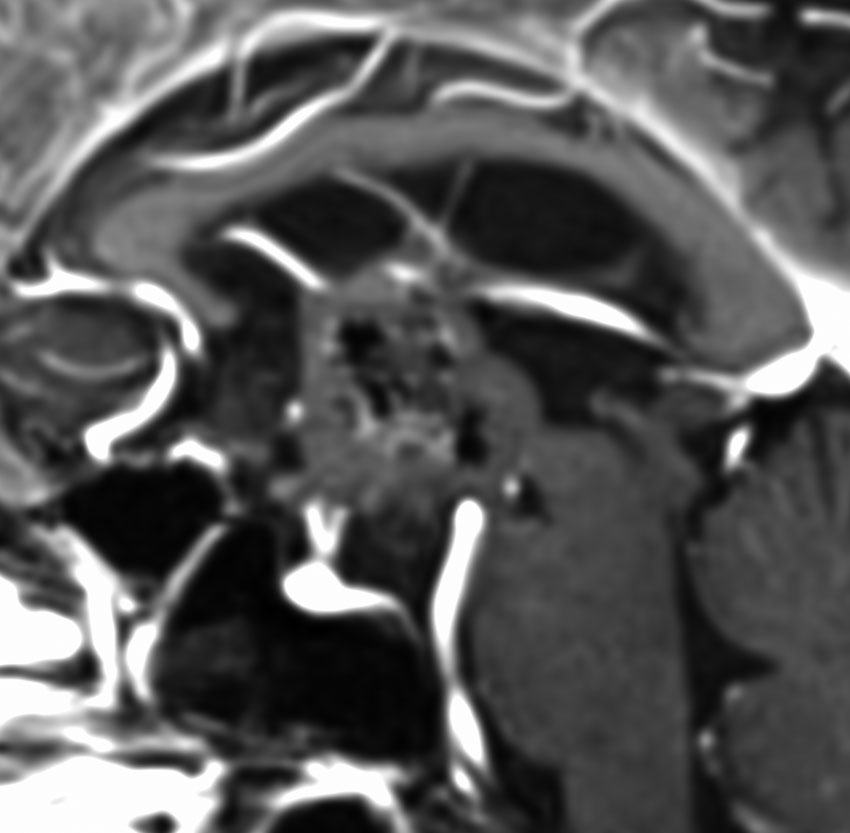

18歳で発症して,60歳まで無治療の大きな視床下部毛様細胞性星細胞腫

hypothalamic pilocytic astrocytoma

1968年 18歳の時に頭痛嘔吐で発症しました。第3脳室腫瘍と閉塞性水頭症の診断だけで,シャント手術を受けました。手術も化学療法も放射線治療もされていません。下の画像は60代で撮影されたものです。この例では,第3脳室内に増大した大きな毛様細胞性星細胞腫が,視床下部下垂体障害を出すことなく,自然経過で増大停止 growth arrest して,カチカチに固まってしまうということを教えてくれます。でも,こんなに都合よく経過観察できる例も珍しいです。

CTでは強い石灰化があります。右のT2強調画像では腫瘍は等信号,視交叉の後ろにあります。内部の低信号は石灰化です。

T1強調画像では等信号,ガドリニウム増強でごく一部がまだらに増強されます。